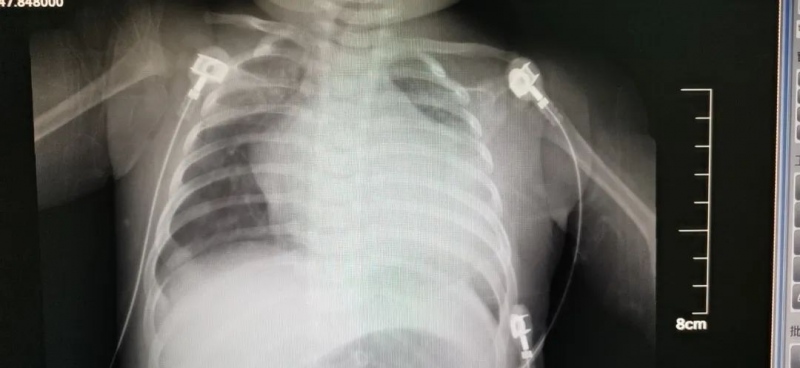

2月中旬,小新忽然呈现喘气快,不爱吃奶,脸色发青的症状。这可急坏了小新爸爸妈妈,尽管疫情严峻,仍是赶忙带着孩子去了当地某三甲医院,其时医师查看发现小新的心脏比较同龄孩子“大”的多,考虑孩子患有先心病、重症肺炎。但通过当地医护人员几天的抗感染、强心利尿等对症处理,小新的病况却没有明显好转。当地医院无法,主张其前往青岛妇儿医院心脏中心就诊。

完善相关查看后,心脏中心医护人员发现:开始床旁急诊超声查看提示小新的左冠状动脉来源反常,射血分数仅30%(正常50-70%)。这是一种十分严峻的杂乱先心病,一般前期不易发现,呈现症状后心脏扩展很明显,因为生后一两个月肺动脉压力的下降,反常来源于肺动脉的左冠状动脉呈现逆灌,导致左心供血缺乏,缺血缺氧导致扩张,严峻的还呈现二尖瓣腱索开裂,瓣叶挛缩,心功能急剧恶化,许多被误诊为扩张性心肌病或心内膜弹力增生症,假如不及时手术医治,心衰持续加剧,或许猝死。

医务人员进一步为患儿进行CTA以及心导管造影,清晰小新便是患有左冠状动脉来源反常。这是一种发现即需求尽早手术的亚急诊手术,只要通过手术才干抢救生命。